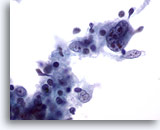

Figure 1

Neck FNA, benign cyst.

An admixture of cells including benign squamous cells and smaller inflammatory cells are present. Also abundant keratin is seen. 20x

Neck FNA, benign cyst.

An admixture of cells including benign squamous cells and smaller inflammatory cells are present. Also abundant keratin is seen.

20x